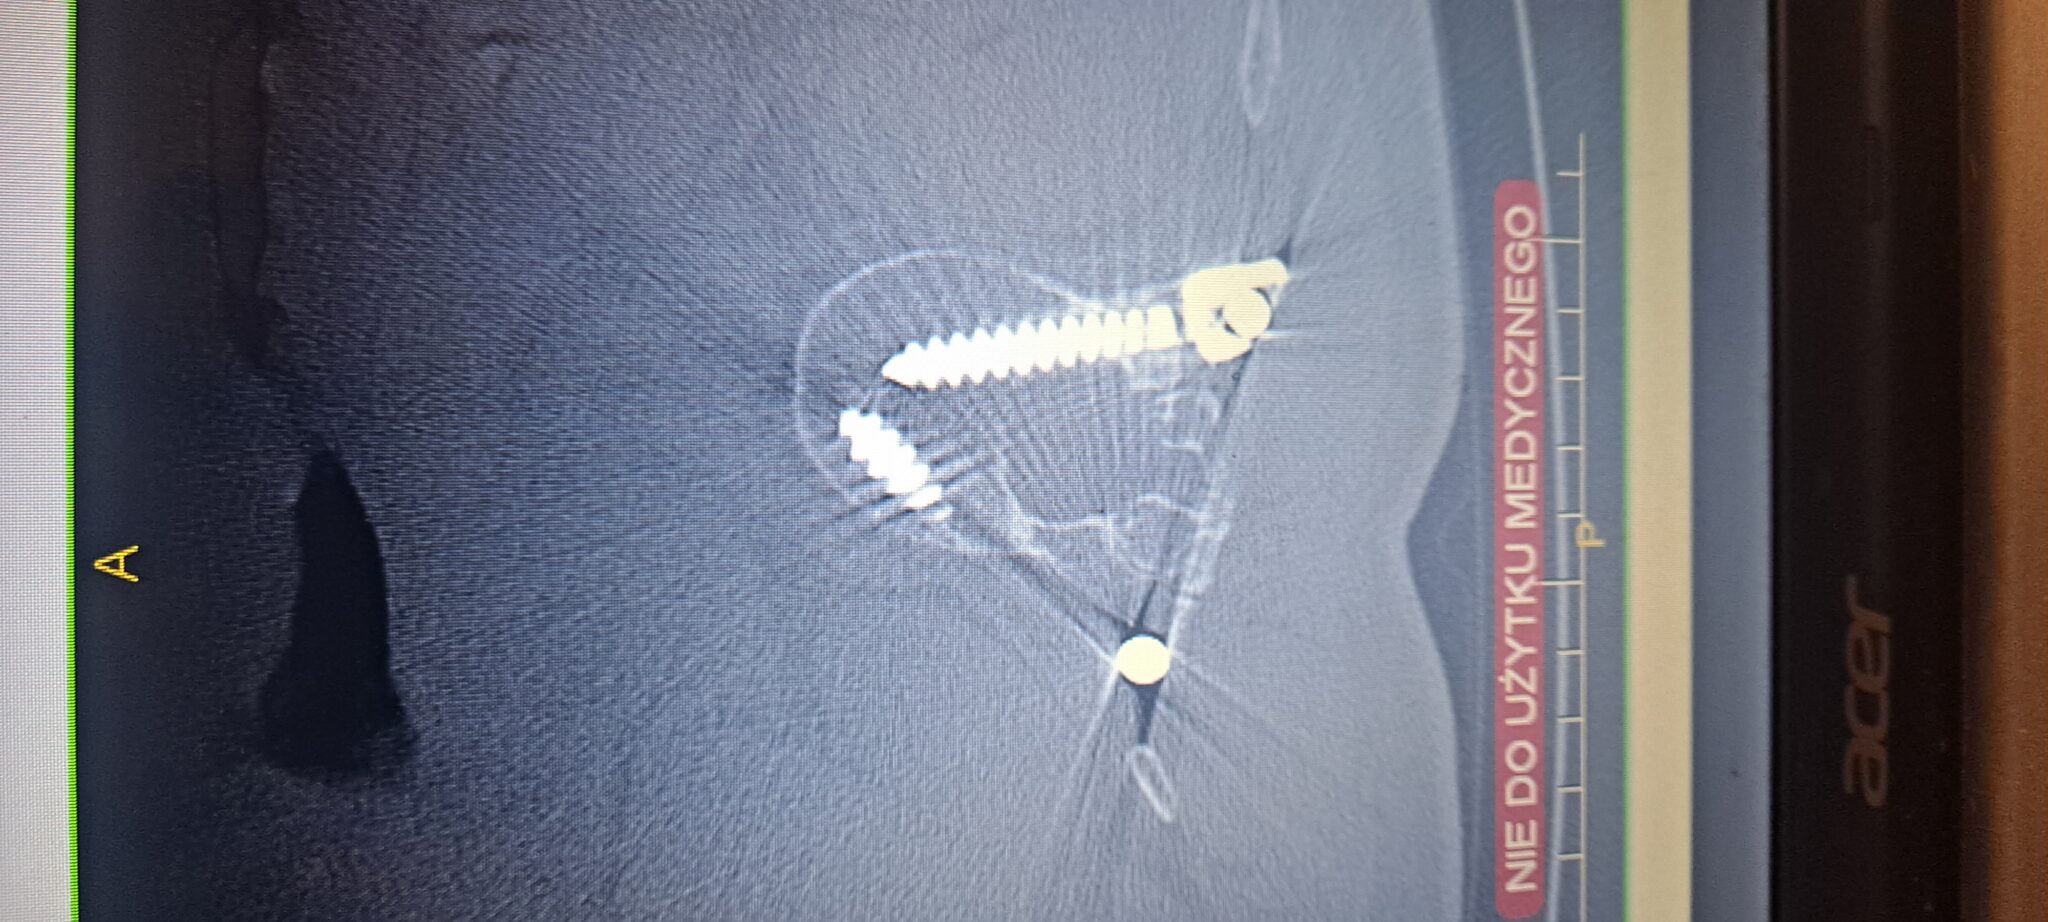

Nazywam się Emilia, mam 35 lat i od dzieciństwa zmagam się z ciężką skoliozą, przepukliną lędźwiową, guzkami Schmorla oraz osteofitozą krawędziową. Przeszłam wiele operacji i rehabilitacji, ale moja walka o życie bez bólu wciąż trwa. W 2024 roku przeszłam cztery kolejne operacje kręgosłupa. Podjęłam decyzję o wszczepieniu neurostymulatora rdzenia kręgowego, który miał pomóc mi funkcjonować bez bólu. Niestety, podczas operacji doszło do śródoperacyjnego zakażenia bakterią pałeczka ropy błękitnej, co zapoczątkowało dramatyczną walkę z infekcją. Zastosowano ciężką antybiotykoterapię, jednak konieczne było usunięcie neurostymulatora i kilkukrotne czyszczenie kręgosłupa. W tym czasie byłam hospitalizowana w szpitalu MSWiA oraz na oddziale Neurozakażeń Szpitala Zakaźnego w Warszawie. Każdego dnia przechodziłam zabiegi w komorze hiperbarycznej oraz odciąganie płynów z kręgosłupa.

Choć zrobiłam wszystko, by wrócić do sprawności, komplikacje po operacji doprowadziły do obluzowania się śrub stabilizujących, które teraz muszą zostać pilnie wymienione. Stabilizacja była wykonywana komercyjnie, dlatego istnieje duże prawdopodobieństwo, że również za kolejną operację będę musiała zapłacić samodzielnie. Jestem samotną mamą 12-letniego syna i każdego dnia staram się być silna dla niego, mimo niewyobrażalnego bólu.